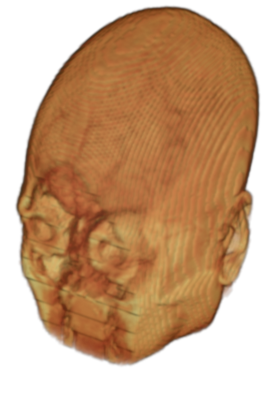

To prevent these types of attack, medical scans are currently de-identified using crude removal-based techniques [Bischoff-Grethe et al.(2007)Bischoff-Grethe, Ozyurt, Busa, Quinn, Fennema-Notestine, Clark, Morris, Bondi, Jernigan, Dale, Brown, and Fischl, Schimke et al.(2011)Schimke, Kuehler, and Hale, Milchenko and Marcus(2013)] which seek to remove privacy-sensitive parts of the head (examples in Figure 3). However, as we demonstrate, these existing techniques fail to reliably hide the patient’s identity – or they are so aggressive that they impair further medical analyses. A better solution is needed.

Benchmark De-Identification Methods. We compare our result with three publicly available and widely-established methods for de-identification of MRI head scans, depicted in Figure 3. All methods have in common that they (1) are not deep-learning-driven, (2) require no additional training and (3), are used on a day-to-day basis in neuroscience and clinical research. All procedures were applied with default settings on images of resolution . The methods include QUICKSHEAR [Schimke et al.(2011)Schimke, Kuehler, and Hale], FACE MASK [Milchenko and Marcus(2013)], and DEFACE [Bischoff-Grethe et al.(2007)Bischoff-Grethe, Ozyurt, Busa, Quinn, Fennema-Notestine, Clark, Morris, Bondi, Jernigan, Dale, Brown, and Fischl]. Descriptions of the methods are provided in the Appendix. We also include MRI WATERSHED [Ségonne et al.(2004)Ségonne, Dale, Busa, Glessner, Salat, Hahn, and Fischl], a skull-stripping method that removes everything except the brain.

A handful of de-identification techniques exist for MRI scans, which are conventionally used for sharing and distribution of MRI data. These existing methods rely on a removal approach to privacy. DEFACE [Bischoff-Grethe et al.(2007)Bischoff-Grethe, Ozyurt, Busa, Quinn, Fennema-Notestine, Clark, Morris, Bondi, Jernigan, Dale, Brown, and Fischl] estimates the probabilities of voxels belonging to the face based on an atlas of healthy control subjects. The scan is de-identified by setting intensities of voxels whose probabilities are small enough to zero. QUICKSHEAR [Schimke et al.(2011)Schimke, Kuehler, and Hale] is a fast but simple approach that computes a hyperplane to divide the MRI into two regions: one containing facial structures, and the other containing the brain of the scan. Voxels in the first part are set to zero. FACE MASK [Milchenko and Marcus(2013)] uses a filtering method to blur the facial features. These existing de-identification approaches are based on traditional computer vision techniques; we believe that the proposed algorithm is the first to adopt a learning-based approach.